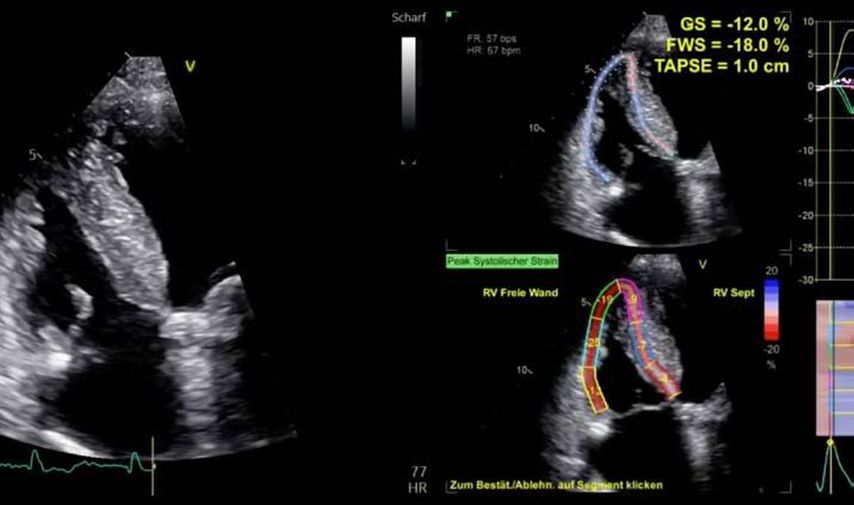

Die moderne Echokardiografie bietet die Möglichkeit einer hämodynamischen Evaluation in Ruhe wie auch bei „point-of-care“-Belastung. „Strain imaging“ und „myocardial work“ können neben bekannten Parametern, wie der Ejektionsfraktion (EF) und der Myokardmasse, ergänzend zur Diagnostik von Herzerkrankungen beitragen.

Im Echolabor des Pyhrn-Eisenwurzen Klinikums Steyr wird jede Form der Myokardwandverdickung mittels einer vollständigen Standardechokardiografie untersucht.2 Dabei wird auch ein Fokus auf die kontrastmittelunterstützte Sonografie gelegt, um die tatsächliche Dicke des Myokards zu vermessen.3 Die Verdickung sollte optimalerweise mittels 3D-LV-Massenmessung erfolgen. Die Messung im 2D-Bild ist dahingehend unterlegen. Ebenso wird jede Myokardwandverdickung mittels 2D-„strain imaging“ in der transthorakalen Echokardiografie (TTE) untersucht.4–6 Der „strain“ ist eine Messung der longitudinalen Funktion des Herzens (Video 1).

Andere Formen der Myokardwandverdickung, die mit „strain“ und MRT gut dargestellt werden können, sind einerseits die Differenzierung der Auswirkung der arteriellen Hypertonie (weiblich, 72a) bei Vorliegen einer Herzinsuffizienz mit normaler EF, einem GLS von –15,4%, einem LA-„strain“, in Reservoirphase 25% bei gering verlängerten T1-Zeiten im MRT. Andererseits kann Steroidabusus (männlich, 44a) zu einem reduzierten „strain“ mit gering verlängerten T1-Zeiten und einer Normalisierung der bildgebenden Befunde nach 2 Jahren nach Absetzen führen bzw. eine Mitochondriopathie (männlich, 32a) zu einer unklaren Myokardverdickung mit diffus reduziertem „strain“ und reduzierter LV-Funktion.4,11,12